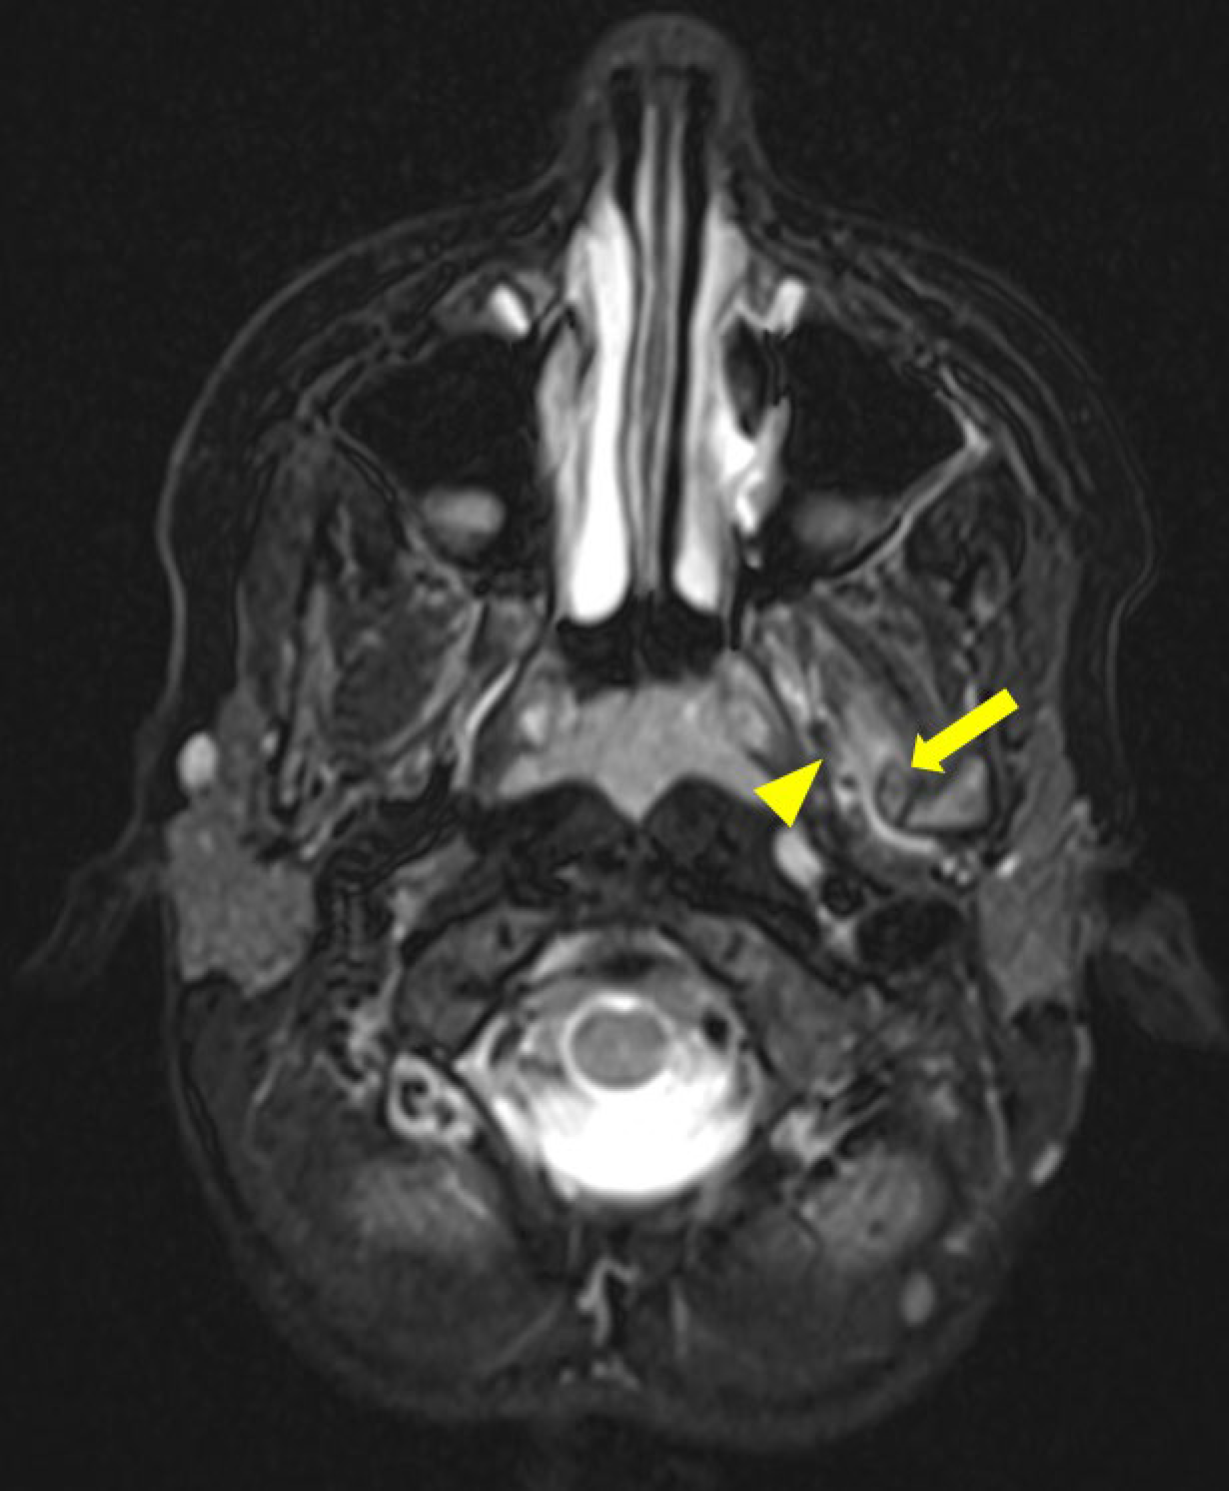

Magnetic resonance imaging (MRI) demonstrated a bony signal intensity of this ossified structure located between the left mandibular ramus and the spine of the left sphenoid (Figure 2). There was a reactive edema around the periphery of the structure, partially infiltrating the fibers of the lateral pterygoid muscle (Figure 3). There was an absence of a cartilaginous cap, suggesting an exostosis.

Figure 3

Axial T2 Dixon MRI scan showing edema infiltrating the lateral pterygoid muscles fibers (arrowhead) close to the ossified sphenomandibular ligament (arrow).